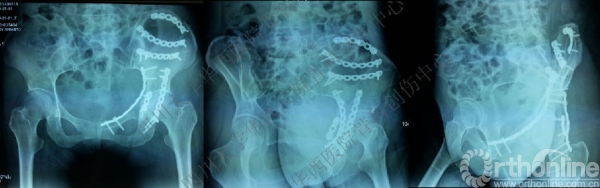

术后X线片

这是术后的X线片,患侧正位、髂骨斜位、闭孔斜位。